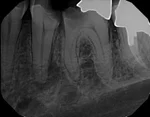

Periapical (PA)

Periapical means “around the apex of the tooth” or around the root. These x-rays are focused on a specific tooth or area to show the entire tooth including the root. This allows us to diagnose any pathology or infection that may be occurring at or near the tooth.

These are usually taken if there are symptoms or a problem noticed, or simply to monitor previous root canals or dental implants periodically. We also may use these x-rays to confirm there is no underlying problem with the tooth before we restore it with a large filling or a crown.